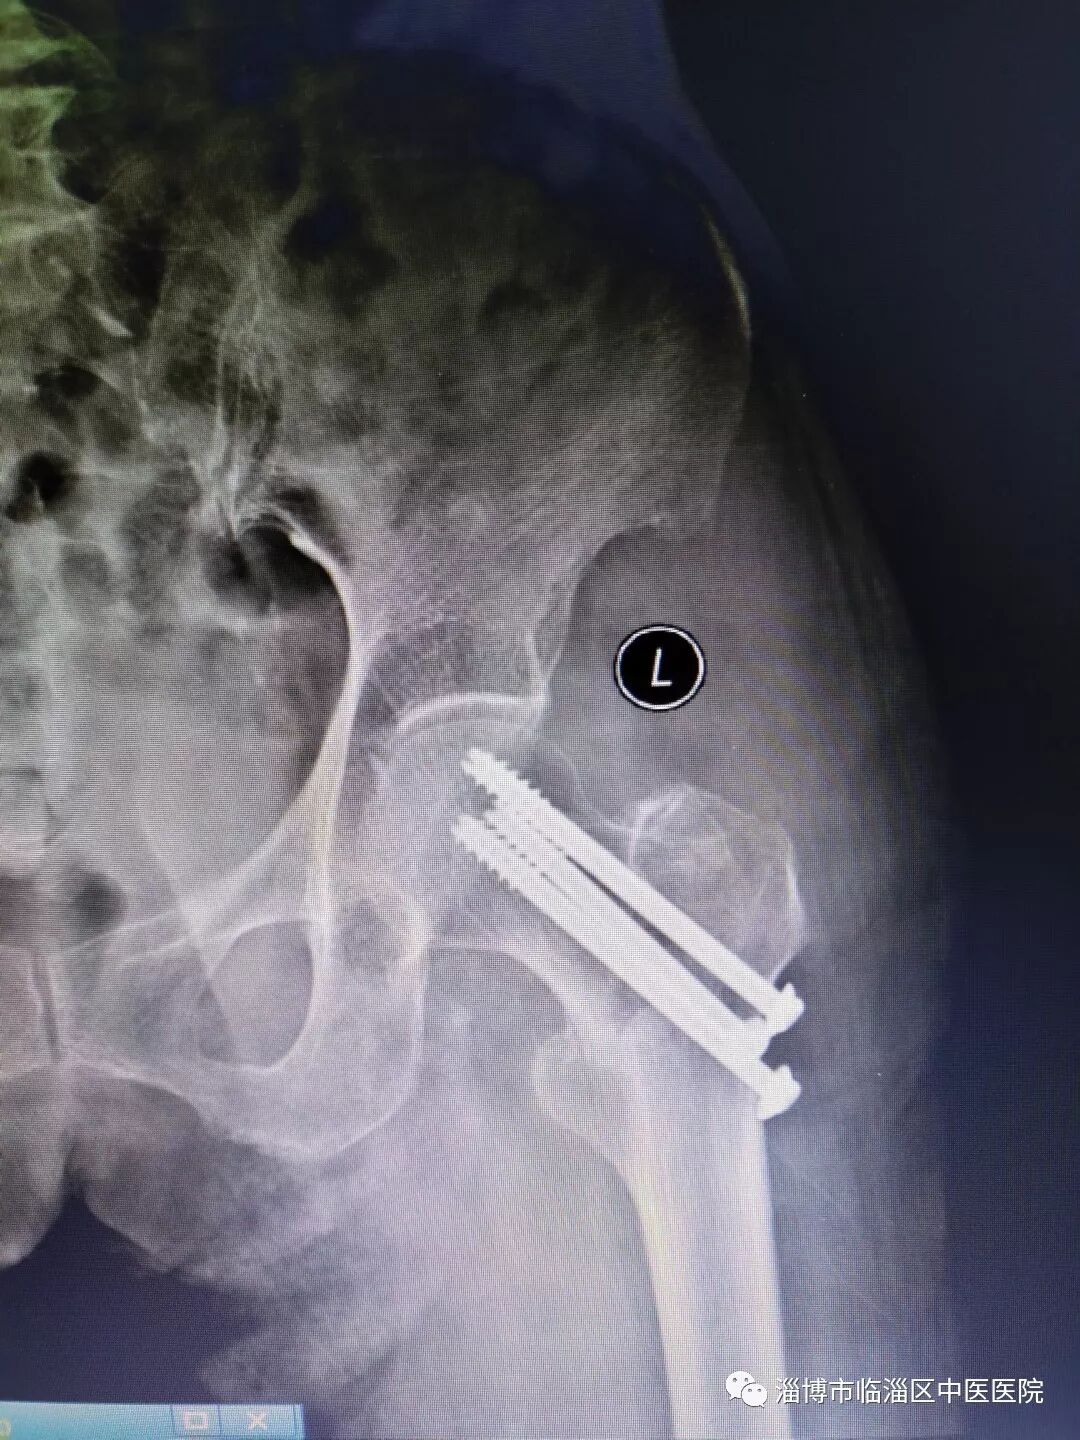

最终,在医护人员的全力治疗下,91岁高龄患者成功在超声引导股神经阻滞及椎管内麻醉下行股骨颈骨折切开复位空心钉内固定术,术中采用微创小切口技术,术后经过一段时间的留院观察与护理,现已恢复出院。

手术后